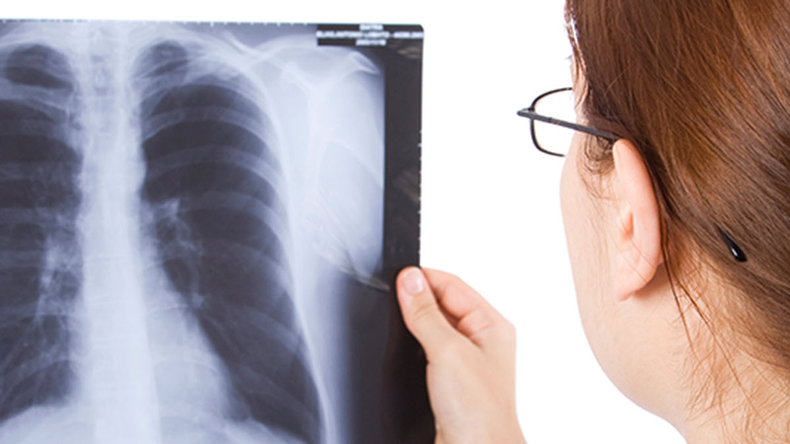

La funcionaria recalcó que el tratamiento de la tuberculosis es efectivo y gratuito, y que se realiza un seguimiento constante por parte del equipo de salud. Además, se efectúan controles complementarios, como radiografías y consultas con especialistas, para garantizar la recuperación total del paciente.